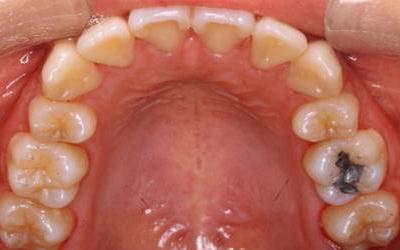

歯並びは正常な位置に生え揃うことが理想的ですが、さまざまな原因で下のように歯並びが乱れてしまう場合もあります。

矯正歯科の目的は、歯並びをゆっくりと美しく治し、心身が健康になることです。

矯正治療は長期にわたるために、治療に関するどんなことでも気軽に話し合いながら、丁寧にコミュニケーションをとりながら、正しい歯並びへと治療を進めてまいります。

矯正装置は種類も数多くありますが、当院では患者様の現在の状態やコスト面などにも考慮して、最適な治療計画を提示しながら治療を提供しています。